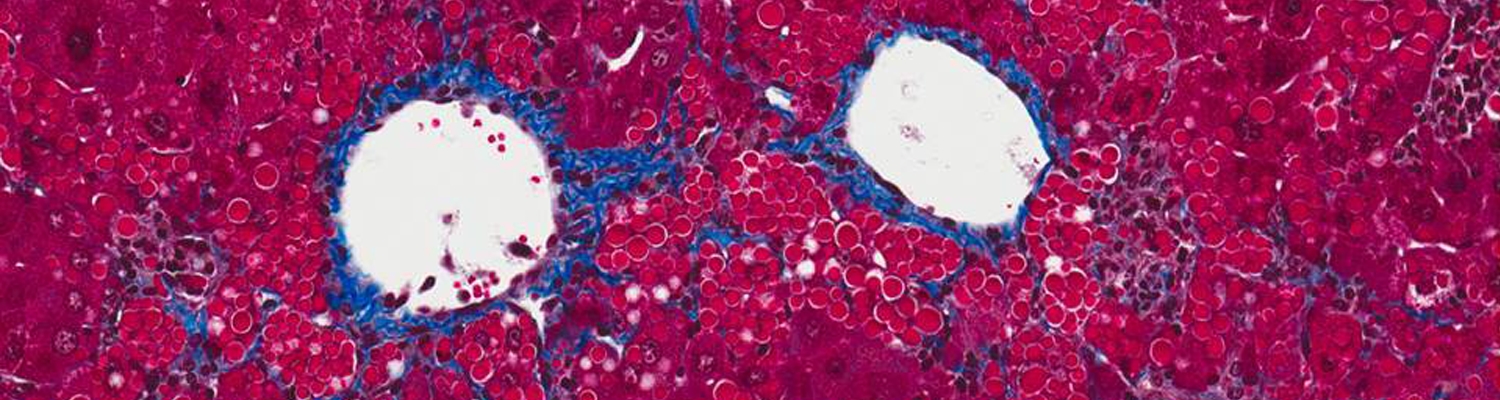

Alpha-1 antitrypsin (AAT) deficiency is a common (although often unrecognized) genetic disease, with up to 4% of the population carrying an abnormal AAT gene. Patients can suffer from either a lung disease, which is caused by a loss of the normal AAT action, or from a liver disease, which is caused by build-up of the abnormal mutant protein (called Z-AAT) within the liver cells.

The laboratories of Drs. Terry Flotte, Guanping Guo,Chris Mueller, Wen Xue, and Mai ElMallah are designing gene therapies to treat the lung disease by replacing the normal AAT protein and now is using a combined gene therapy-RNA interference (RNAi) approach to test a potential treatment for the liver disease. Initial efforts used a gene therapy agent called rAAV8 to deliver a form of interfering RNA called a short-hairpin (shRNA). These studies showed a 50% reduction of the offending mutant Z-AAT protein in a mouse. Subsequently, we have developed potentially less toxic approaches based on incorporating the natural microRNA structure into the short hairpin within the rAAV8 gene therapy agent. These microRNAs were altered to allow them to block production of the toxic Z-AAT. Early results from experiments in mice show that the new strategy reduces the toxic Z-AAT by as much as 80%. We have also designed gene therapy agents that should allow us to simultaneous block production of the toxic Z-AAT and make the healthy AAT protein within the same liver cells. Our immediate goal is to improve the effectiveness of this strategy in mice, while ensuring its safety, with the long term goal of developing these methods into therapy for treating AAT deficient patients.